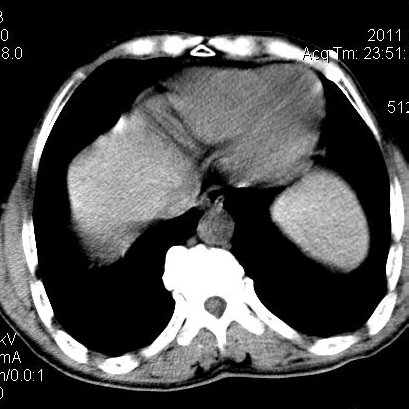

肝左叶发育异常

男性,55岁,骑摩托车摔倒后入院,自述右上腹疼痛

[backcolor=#FF0000]第一次诊断的时候也是这么肯定,可是床旁超声检查并没有发现明显异常,而且患者的一般症状都良好。还好临床只是保守治疗,没有立即手术,第二次复查的时候没有一点变化,又做了MRI检查,没有血肿,

这是一例肝左叶发育异常的,很个性吧~[/backcolor]